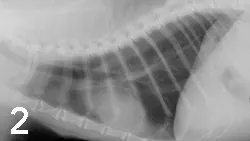

Laboratory Work. A CBC, biochemical profile, urinalysis, thyroxine measurement, and chest radiographs (Figures 1 and 2) were performed. Results of the CBC and biochemical profile were normal, with the exception of high-normal levels of BUN (38 mg/dl; reference range, 6 to 35 mg/dl) and creatinine (2.1 mg/dl; reference range, 0.4 to 1.9 mg/dl). Urinalysis revealed diluted urine (USG 1.019) but was otherwise unremarkable. Serum thyroxine concentration was normal.

Differential Diagnosis. Problems identified include respiratory distress characterized by increased effort and referred upper airway sounds, heart murmur, and anorexia. Differential diagnoses for respiratory distress include upper airway obstruction (including mass or laryngeal paralysis), pulmonary thromboembolism, hyperthyroidism, or other metabolic or systemic disturbances. This case is challenging due to the lack of radiographic abnormalities consistent with most common causes of feline respiratory distress.

A lateral radiograph of a dog's thorax shows the ribcage, heart, and lungs, with clear visibility of the vertebrae and diaphragm. The image highlights the overall lung fields and any potential abnormalities in the thoracic cavity.